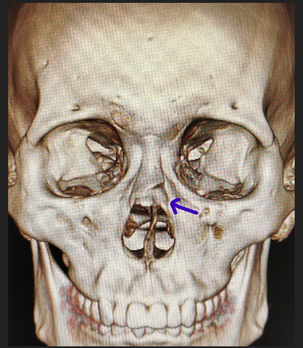

鼻骨骨折 顔面骨骨折の中で最も頻度の高い骨折です。 手術方法 受傷後2~3週間以内であれば、皮膚切開を行わずに整復治療が可能です。整復後はプラスチック製鼻ギプスと鼻内固定を行います。 麻酔 成人なら局所麻酔で処置が可能ですが、お子さんの場合は全身麻酔が必要です。 入院期間 2ヶ月前、事故により、鼻骨骨折を負いました。その5日後、できるだけ元に戻すべく手術を行いました。 しかし、元には戻らず、偏重していることと、若干鼻が低くなったようです。 一昨日、術後経過を診てもらうために、CTを撮ってもらいました。 鼻骨の真ん中の骨がなく、医師には粉鼻骨骨折 ( nasal fracture 或 對正,多半效果不錯。若是和其他結構有關的受傷(第二型及第三型),需加以識別,並且手術 治療 。 預後 鼻骨骨折後約三至四週後鼻子的結構才會穩定。有些專家建議在這段期間內不要戴眼鏡或是擤鼻涕,以免影響骨骼的對正。鼻骨約在四至八週後才會完全融合

らの病態や修正手術を述べる。 Ⅰ.新鮮鼻骨骨折 1 診断 1)臨床症状 鼻骨骨折1)はまず殴られたりぶつかったり転んだ りの外傷の既往があり,視診では鼻部の腫脹,鼻出 血,鼻部の陥凹がみられる。外傷直後で腫脹・浮腫 の強い場合は視診ではわかりにくいので,浮腫や腫 脹がおさまった 鼻骨の骨折・その恐れがある場合の症状 鼻づまり、通りが悪い感じがする 腫れが落ち着くと骨折による変形がはっきりしてきます。骨折による変形を直すには手術が必要です。 3 手術の時期と方法 体には治癒力があるので、変形した状態で骨が固まります。このため、2週間を超える鼻骨骨折整復固定術(非観血術)鼻中隔矯正術 10 鼻中隔血腫切開術 鼻中隔膿瘍切開術肋骨骨折観血的手術 10 *1 手指・足指(MP関節を含まず先端側の場合)を除きます。 *2

About Press Copyright Contact us Creators Advertise Developers Terms Privacy Policy & Safety How works Test new features Press Copyright Contact us Creators 價格需要諮詢具體手術的醫院 14年04月14日 0849 治療單純鼻骨骨折無移位者,鼻腔給予止血可不作其他處理。 有時鼻畸形者應在腫脹發生前或消腫後進行鼻骨復位。 但應在受傷後一周內進行,超過兩周者,因骨痂形成使復位困難。 由於未及時整複後遺畸形骨折ごとの症状、診断・治療方針、手術方法 鼻骨骨折・鼻篩骨骨折 鼻骨骨折(びこつ) 鼻の骨は薄いため「鼻を殴られた」等、比較的弱い力でも骨折します。①鼻血、②鼻すじが曲がる(斜鼻、しゃび)、③鼻が低くなる(鞍鼻、あんび)、④鼻が詰まる

鼻骨骨折是拍x线平片还是ct呢 鼻骨骨折 鼻骨骨折检查

鼻骨骨折影像学诊断